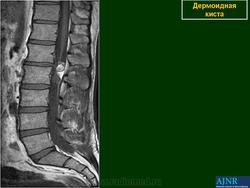

Intra osseous Epidermoid cyst

Imagerie ostéoarticulaire :

site pour les patients

[Image Osteo Articulaire]